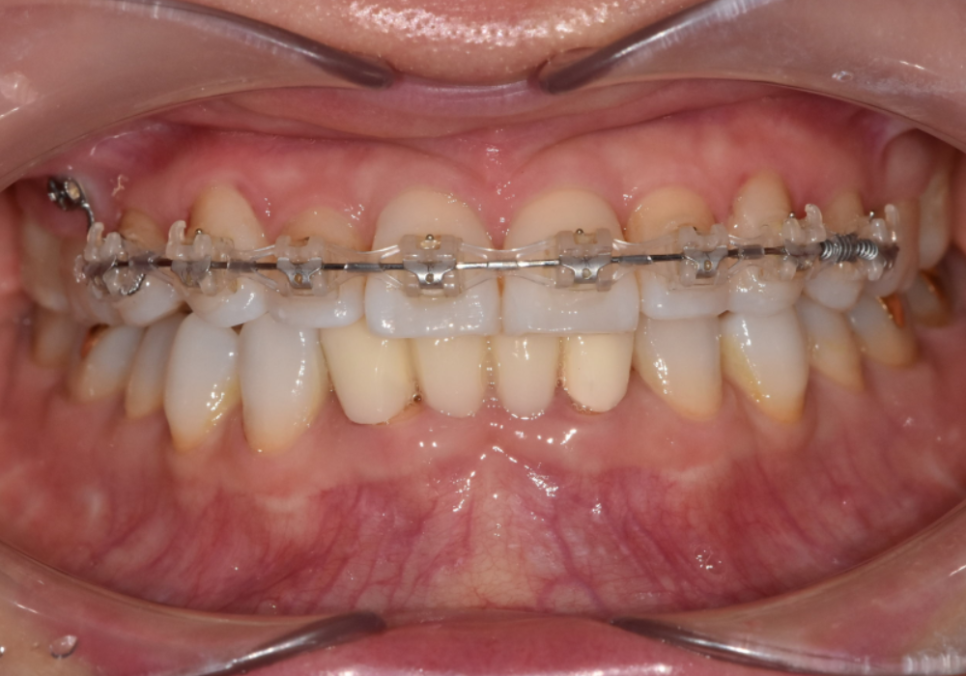

환자분은 긴 교정 기간을 감당하기

어려운 상황이셨고,

이런 실생활의 불편함을

하루빨리 해결하길 원하셨죠.

물론 교정도 방법이겠지만,

현재의 구강 상태를

종합적으로 고려해 보았을 때,

전체적인 치아 배열은 안정적이라,

앞니를 많이 깎아내지 않고도

충분히 배열을 맞출 수 있는 상태였습니다.

전체 치아를 이동시키는 교정 대신,

틀어진 각도만 정교하게

바로잡는 라미네이트로 가닥을 잡았고,

결과적으로 환자분께

가장 만족스러운 대안이 되었습니다.

살짝 틀어져 있던 앞니가 제 자리를 찾고 나니,

미소가 훨씬 단정하고 편안해 보이시죠?